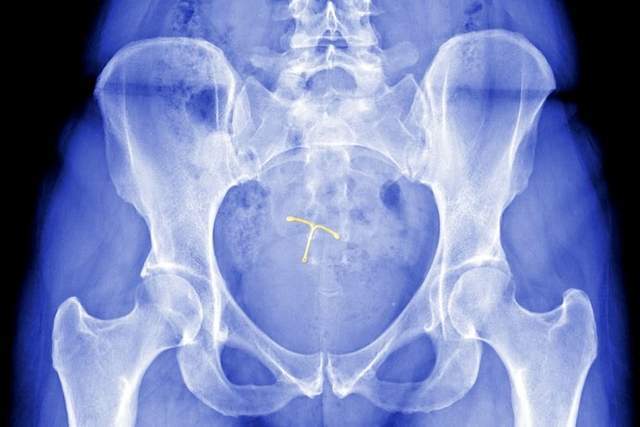

许多母亲应该熟悉宫内节育器。

七八十年代,为了达到避孕的目的,很多女性选择使用宫内节育器。

由于当时避孕药比较少,上避孕环避孕效果相对较好,可以省去很多麻烦,所以女性会选择环疾。